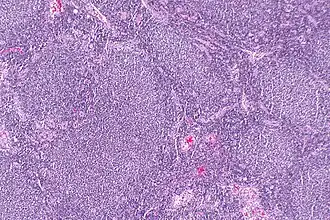

Description de l'image Follicular lymphoma -- low mag.jpg.

Lymphome folliculaire